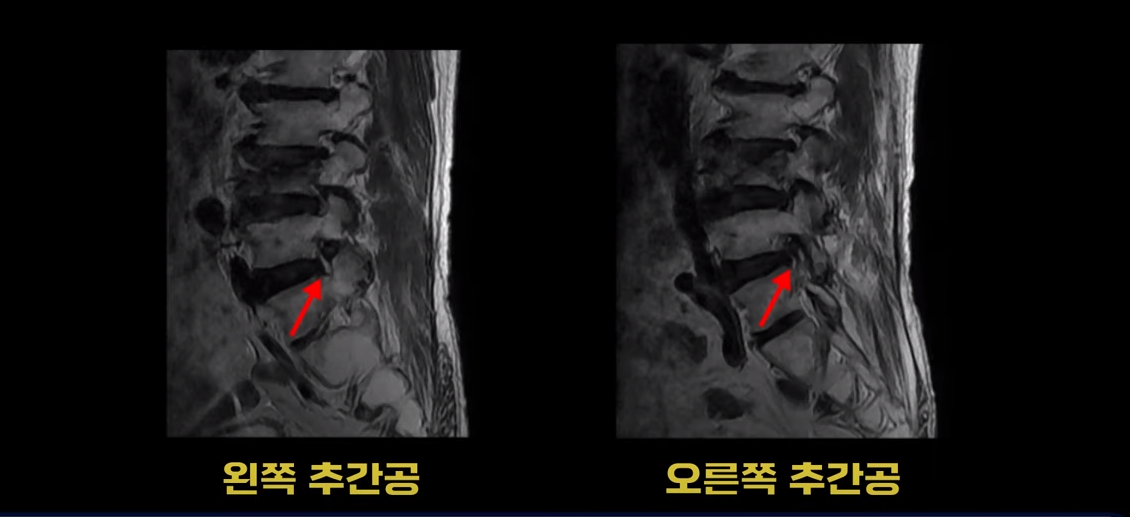

이분 MRI를 보시면 4번 5번과 5번 1번에 협착증수술, 즉 감압술을 한 흔적이 보입니다.

두꺼워진 황색인대를 제거해서 척추관의 공간을 넓힌 것으로 보입니다. 이렇게 수술했어도 신경가지가 척추 좌우로 빠져나가는 추간공은 여전히 노화와 퇴행으로 인해 좁아져 있는 상태입니다.

이런 상태에서 척추가 충격을 받으면 협착증 증상이 심해질 수 있습니다. 이분도 협착증 수술 후에 집에서 넘어지신 후 그 충격으로 척추에 압박골절이 발생하면서 심한 허리 통증이 생기고 동시에 엉덩이와 다리의 협착증 증상이 수술 전보다도 훨씬 더 심해집니다. 그래서 환자분 표현으로는 이제 못 걷게 됐구나라고 생각하셨다고 합니다.